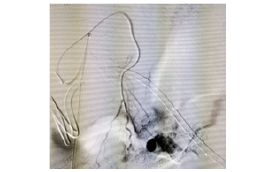

9. Left gastric vein pseudoaneurysm in pt with UGI bleed- embolization

Various other interventional procedures are also carried out in the hospital by the interventional radiology team. In a span of nine months or so, this team has performed procedures like mechanical thrombectomy for stroke, cerebral aneurysms coiling (both ruptured and unruptured), cerebral AVM, cerebral AVF, renal AML embolization, left gastric artery pseudoaneurysm embolization in a patient with upper GI bleeding, and subclavian venoplasty for severe venous stenosis in a CKD patient with brachio-cephalic fistula for dialysis.